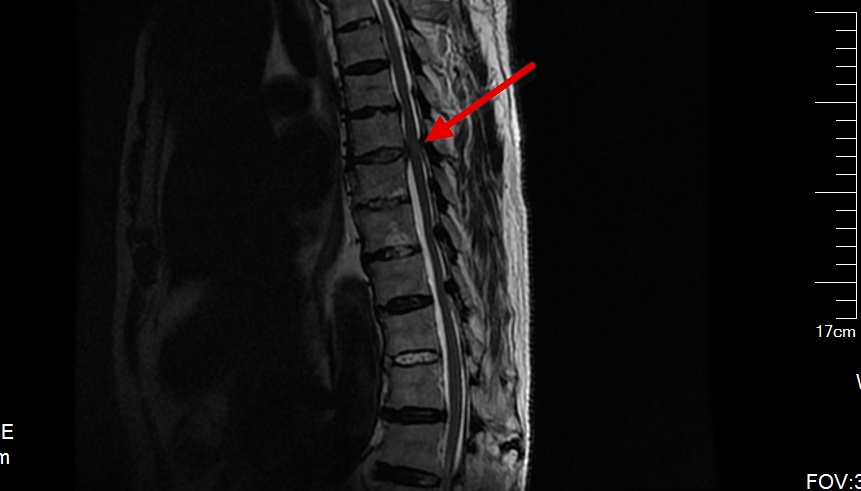

而且,脊柱内镜不仅仅应用于腰椎疾病,胸椎间盘突出和颈椎间盘突出也是很好的适应症,优势更加明显,镜下放大20多倍后,能更精确的操作,避免了神经的损伤。

这是一例胸7-8间盘突出的患者,患者下肢无力越来越重,已经到了不能走路的地步,必须手术才能解决,可是胸椎手术风险比腰椎大的多,是真有可能瘫痪的,我们顶住压力,为了患者的健康着想,为他做了脊柱内镜下胸椎间盘摘除术。

手术很顺利,间盘摘除的很彻底,患者终于又可以站起来走路了。